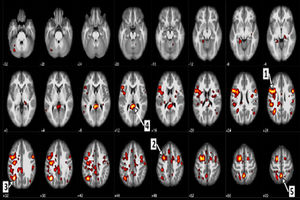

همکاری علمی میان محققان در IBM و دانشگاه آلبرتا در کانادا به ایجاد نرمافزاری منجر شده است که میتواند اسکنهای…